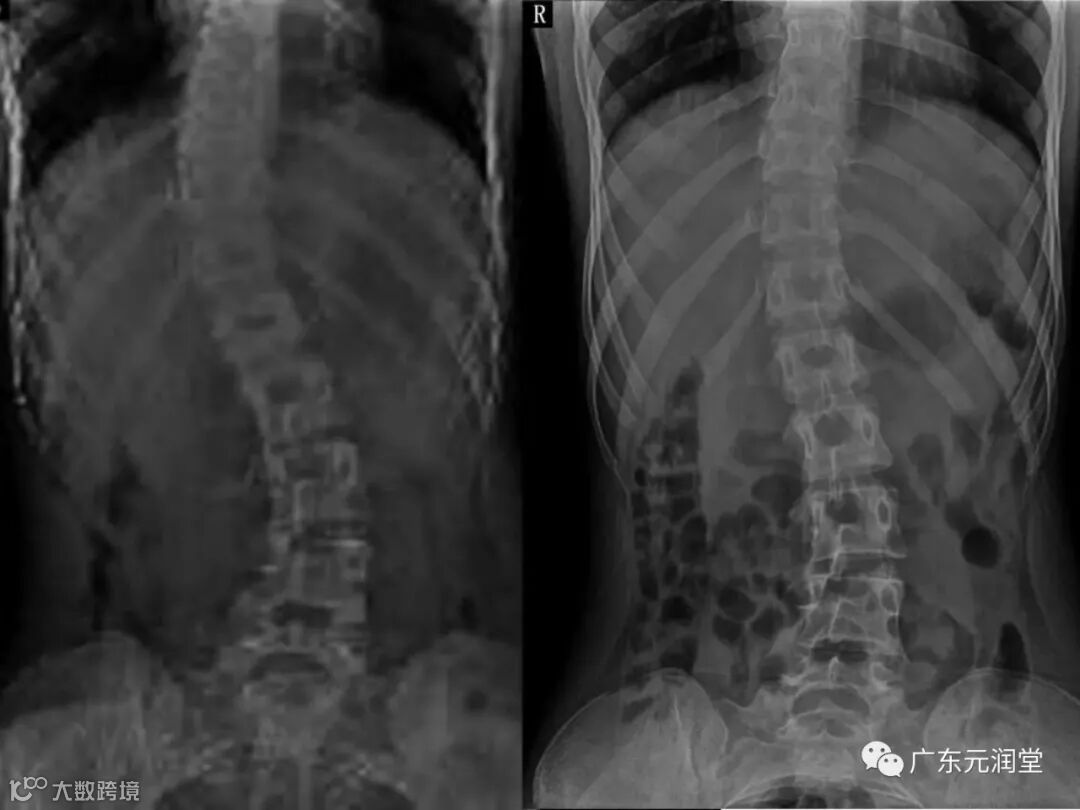

脊柱侧弯定义为脊柱向侧方的异常弯曲,超过10°。从身后观察,正常的脊柱是垂直的。然而,脊柱侧弯的患者从身后观察,侧方或者偏向一侧的弯曲就很明显。图示表明了脊柱向一侧倾斜的外观,但是要与姿势不良区分开。

躯干从侧方观察时候,正常的脊柱会有正常的弯曲存在。当脊柱的下段有前凸存在时候,那样在上胸区域就有正常的后凸存在。当前凸增加时称为过度前凸;上胸段的后凸增加称为过度后凸畸形。从侧方观察出现的异常变化往往伴发脊柱侧弯性变化。在青少年性最常见的脊柱侧弯中胸段的后凸往往是减小的。